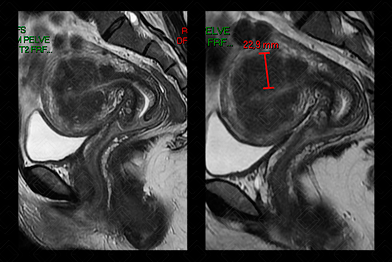

Texto alternativo para a imagem Figura 2. Créditos: Dra. Elazir Mota - Rio de Janeiro/RJ

Descrição da figura 2: Ressonância magnética da pelve, imagem ponderada em T2, sagital, evidenciando zona juncional espessada, com sua espessura acima de 12 mm (medindo 22 mm) e pequenos cistos subendometriais de permeio, compatível com adenomiose.

• Ressonância magnética da pelve feminina : Os principais achados são uma zona juncional com sua espessura superior a 12 mm (pode ou não estar associado a aumento do volume uterino), de permeio a zona juncional espessada observam-se focos hiperintensos, nas imagens pesadas em T2, estriações lineares. Observação: devemos lembrar, ainda, que existe a adenomiose focal (ou adenomiose de Cullen).